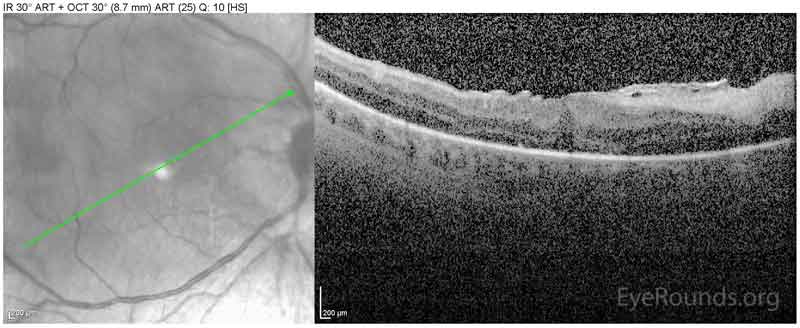

Spectral-domain OCT obtained the same day as the above photograph demonstrating development of an epiretinal membrane with distortion of the foveal contour.

Figure 4. Spectral-domain OCT obtained the same day as the above photograph demonstrating development of an epiretinal membrane with distortion of the foveal contour.